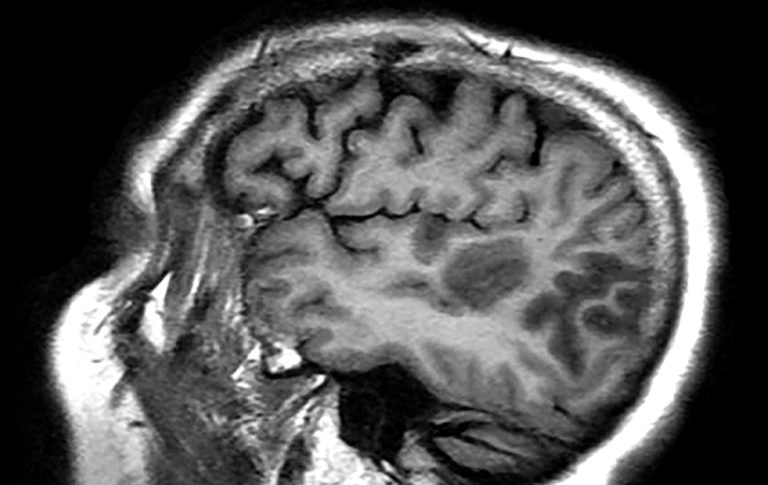

Maternal SARS-CoV-2 Infection Linked to Neurodevelopmental Diagnoses

Neurologic Manifestations of Zika Virus Infection: What We Know So FarJonathan Miner, MD, PhD, and Karin Nielsen-Saines, MD, MPH, discuss the latest insights about neurologic complications of ZVI and knowledge gaps that still exist in this field.

Improving Pediatric Stroke Diagnosis: Filling the GapsBecause of the relative rarity of stroke in children, many clinicians tend to presume that mimics are the cause of the symptoms.